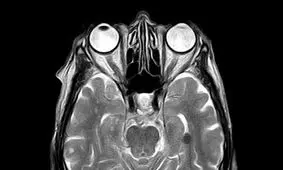

نتایج یک مطالعه نشان میدهد که ویروس کرونا میتواند مغز انسان را تا ۱۰ سال پیرتر کند یا از ضریب هوشی بکاهد.

یافتههای اخیر محققان توضیح میدهد که چرا ضربه به مغز بسیار مضر است و چگونه میتواند اثرات طولانی مدتی داشته باشد.

نتایج پژوهشی که بهتازگی منتشر شد نشان میدهد که سردرد، سرگیجه، و هذیانگویی که از علائم مبتلایان به ویروس کروناست…